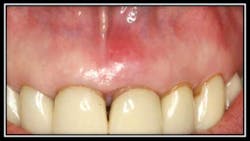

Case #2: Horizontal Hair Line Fracture #19

By Robert Gottlieb, DDS, and Suzanne Newkirk, RDH